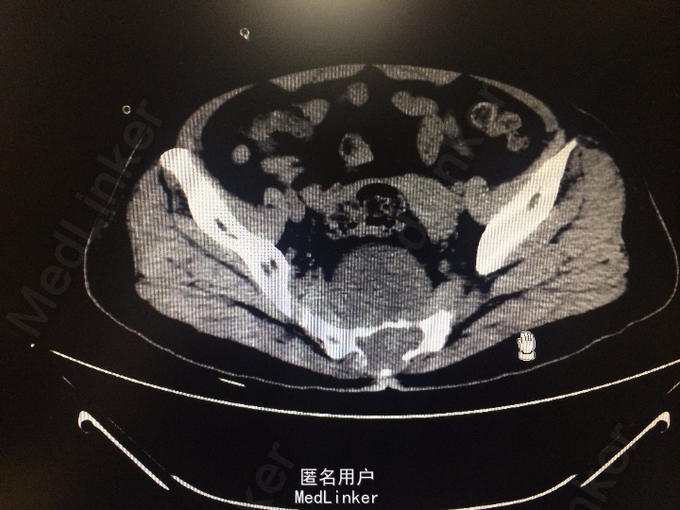

老年女性 主诉:腰背痛半年余,大小便失禁1周。 病史:患者于半年前腰部扭伤后,出现腰痛、腰部无力,需借助外力站立和行走。自诉四肢肌肉力量间断出现减弱,容易出现肌肉僵直,并有肌肉颤动感。半年来,患者多卧床休息,未接受正规治疗。10余天前,出现胸部疼痛,并向背部放射,病人烦躁、易怒,难以入睡、胃纳差、大便次数少。1周前出现大小便失禁,体重近1月下降10余斤。

查体:脊柱生理弯曲存折,腰椎棘突间触痛(-),双侧腰椎旁叩痛(-),活动自如,关节无红肿,双侧下肢肌群肌力正常,双侧下肢外侧皮肤痛、温觉正常,未引出病理性反射,尾骨未触及。 辅查:外院X线:腰骶角增大,提示腰椎失稳可能;腰椎轻度退行变;S3以下骨质结构缺如。

诊断:骶尾部肿物:脊索瘤? 处理:完善各项检查后,为明确具体病理类型行骶尾部肿瘤穿刺活检术,病理明确后行腹腔镜辅助下骶尾部肿瘤切除术。